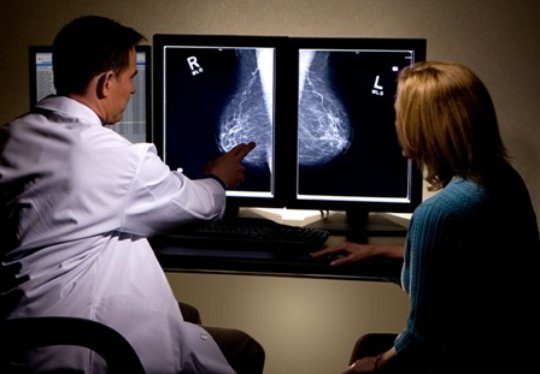

Relación entre el tamaño del cáncer de mama y su pronóstico

12 junio 2017

Los tumores pequeños tienen una probabilidad mayor de tener características biológicas favorables y de no progresar durante la vida de la paciente. New England Journal of Medicine, 8 de junio de 2017